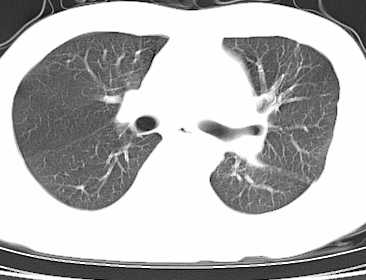

二周前患者无明显诱因出现咳嗽,多为刺激性干嗽,无咯血,伴心悸,低热,夜间无明显盗汗,消瘦明显

年龄?左侧胸腔中量积液,左下肺见有较多斑片状和大片状影,伴有支气管充气征,考虑:1、左下肺炎;2、结核。肿瘤可以基本排除。

考虑:1、左侧中量胸腔积液伴左肺下叶肺膨胀不全、炎症。

2、心包积液。

左侧中量胸腔积液伴左肺下叶肺膨胀不全、上肺外围多个小囊样腺泡样病灶。考虑化脓炎症。

心包积液没有,纵隔积液。

1、左侧中量胸腔积液伴左肺下叶肺膨胀不全、。

3 无纵隔肿大淋巴结.

患者刺激性干嗽,无咯血,伴心悸,低热,夜间无明显盗汗,消瘦明显,左侧中量胸腔积液伴左肺下叶肺膨胀不全、上肺外围多个小斑片病灶。考虑肺结核可能性大。

左肺舌叶及下叶见斑片状,大片状高密度影并相应处胸膜及心包不规则增厚,左肺下叶膨胀不全。右肺未见异常,双肺段以上支气管通畅。纵隔左移,其内未见明显肿大淋巴结。左侧胸腔积液。

1.考虑:左肺化脓性炎症。2.左侧胸腔积液(中等量)。3.心包炎症。